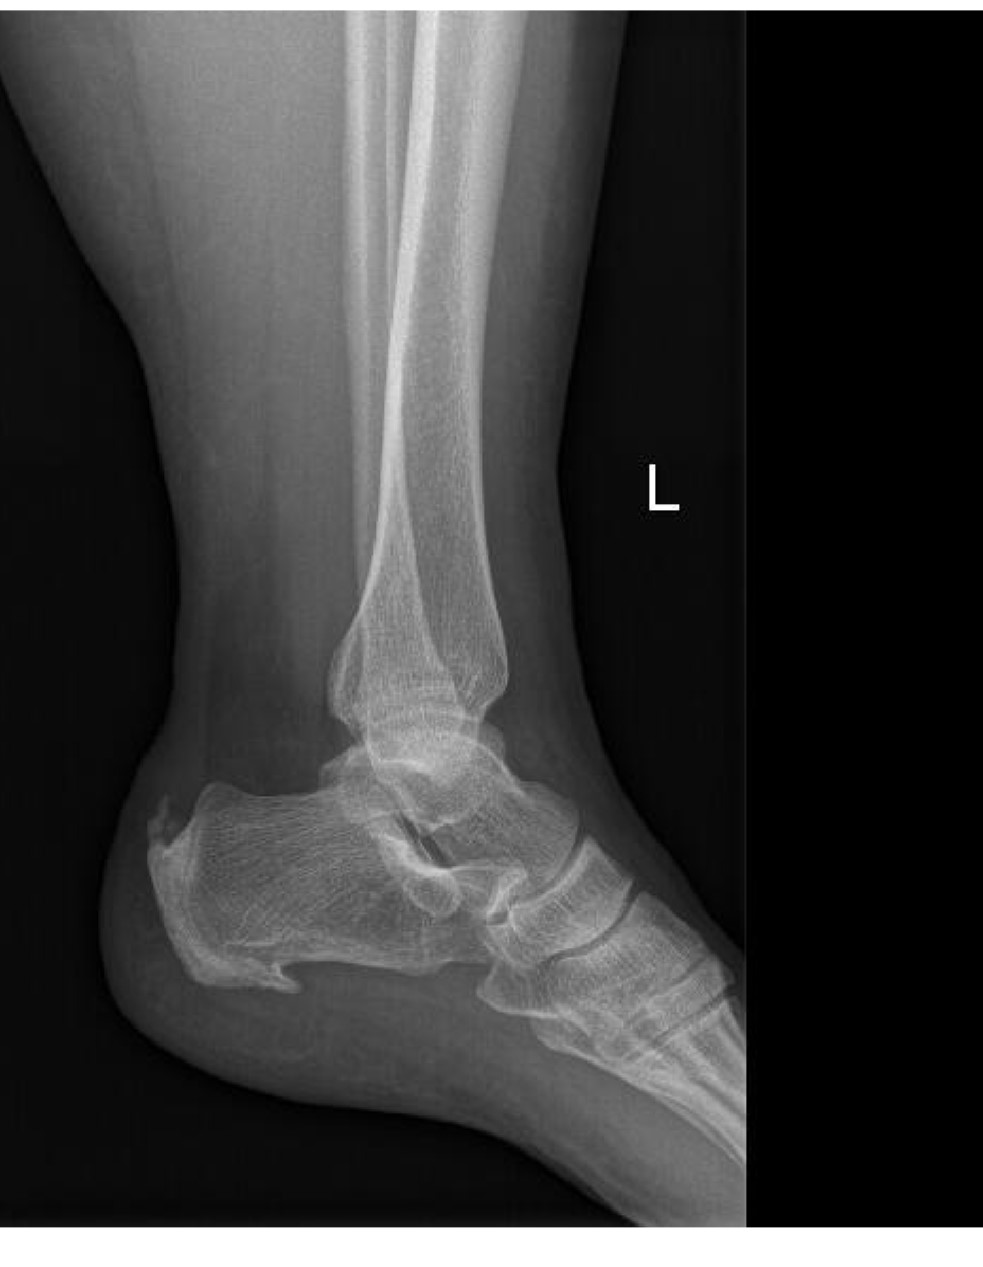

Pruebas complementarias

Radiografía pies bilateral: se observa osteofito en la inserción del tendón de Aquiles, de morfología espiculada, compatible con espolón aquíleo.